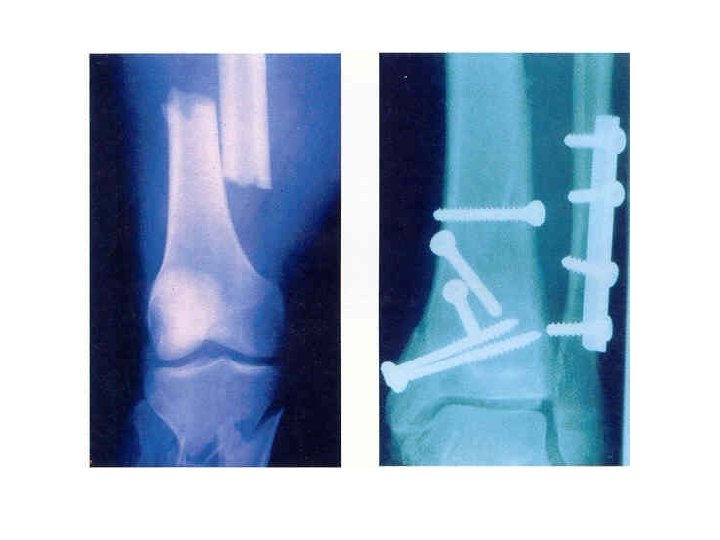

Fractures Simple (Closed): Compound (Open):